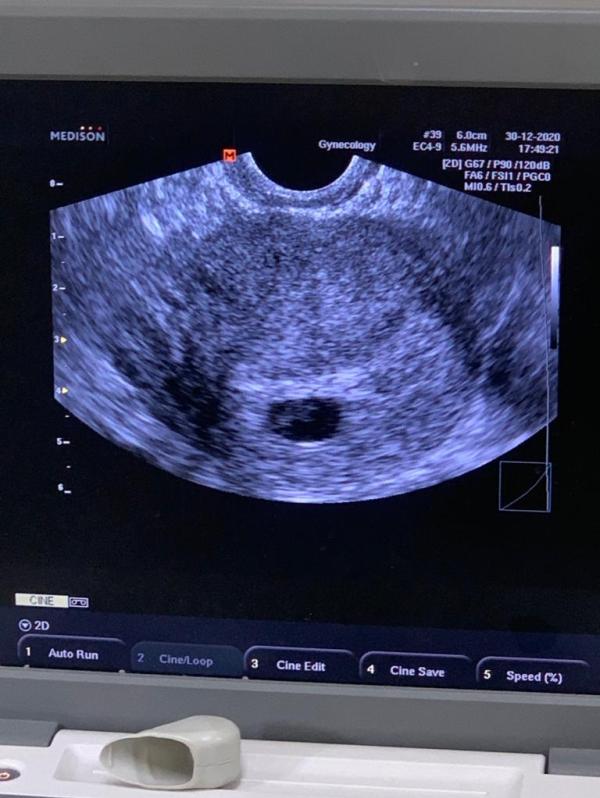

Девочки, врач отправила мне вчерашние фотки.. У кого были двойни, так ли было на 5-6 неделях? Меня смущает их размеры-один побольше, другой поменьше, третьего и не видно..

Она сказала похоже на тройняшек, но 2 точно есть

Скорее всего которое больше, там близнецы) а третий уже разнояйцевый двойняшка)

@cernoglazaya не) имеется ввиду что 2 детишек однояйцевых и в одном плодном пузыре, а 3ий в отдельном пузыре

@katrin757 аа, поняла вас.. Просто там где побольше, сказала 6 недель и серцебиение уже заметно